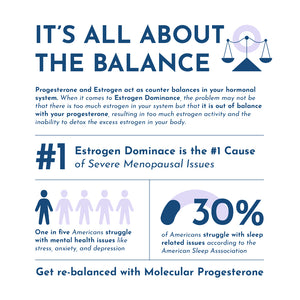

Estrogen can trap you in an endless state of thyroid dysfunction that can seem impossible to escape.

Progesterone can help free you from estrogen dominance and boost your thyroid all while promoting deeper sleep, protecting against stress & anxiety, supporting healthy joints, and so much more!

Estrogen Dominance can happen at any one of the following stages or be present during all three.

Our bio-identical progesterone is designed and formulated like no other. Unlike progesterone creams that are typically low concentration or contain thyroid suppressive oils, or progesterone pills / tablets that are largely inactivated by your liver, or suppositories that are prone to crystallization and can’t be absorbed… Progesterone Oil solves all of these problems. It’s highly concentrated at more than 10% progesterone, doesn’t crystalize, and contains a special solution allowing for close to 100% absorption. The secret lies in the special formulation with Vitamin E, which acts as a carrier to deliver the progesterone directly into the bloodstream. This makes it the quickest and most absorbable bio-identical progesterone source available.